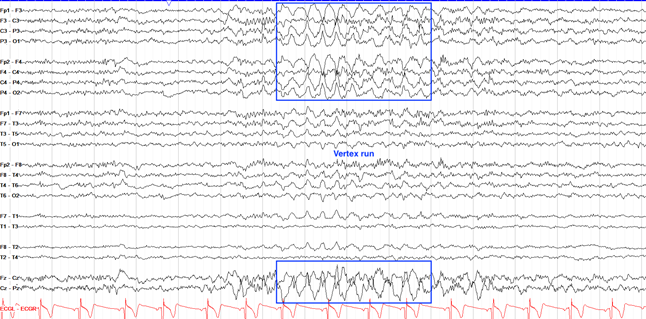

婴儿痉挛症

Lennox-Gastaut综合征

BECTS

失神性癫痫